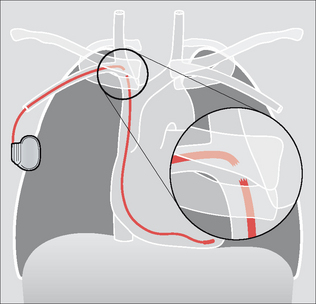

PACEMAKER CHECKLIST—THE LATERAL CXR

1. Ventricular lead:

image The tip should be directed anteriorly and inferiorly (Figs 12.13 and 12.14).

2. Atrial lead:

image The lead should have a smooth anterior curve as it is projected over the heart (Fig. 12.15).

image The electrode tip should be angled superiorly—i.e. positioned in the right atrial appendage (Figs 12.15 and 12.16).

image

Figure 12.13 Normal position of a ventricular lead.

Figure 12.14 Normal position of a ventricular lead. (Retouched.)

Figure 12.15 Dual chamber pacemaker. Normal positions of the atrial and ventricular leads.

Figure 12.16 Dual chamber pacemaker. Normal positions of the atrial and ventricular leads. (Retouched.)